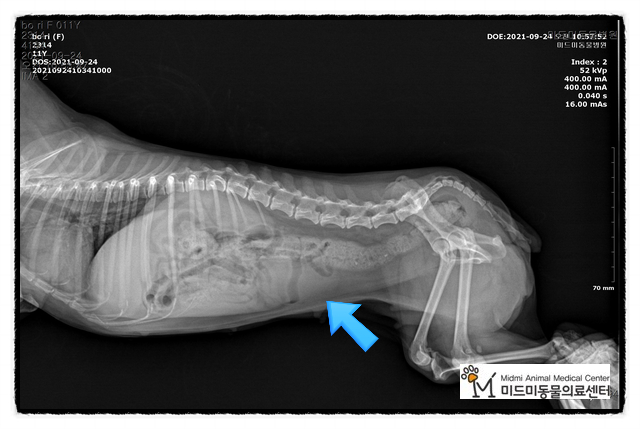

저희 병원에서 방사선, 총음파 검사 후 개의 자궁 축농증으로 진단되었습니다.

수술 전 혈액검사, 초음파검사, 방사선촬영을 통해 수술 전 컨디션을 체크한 후 수술을 결정했습니다.